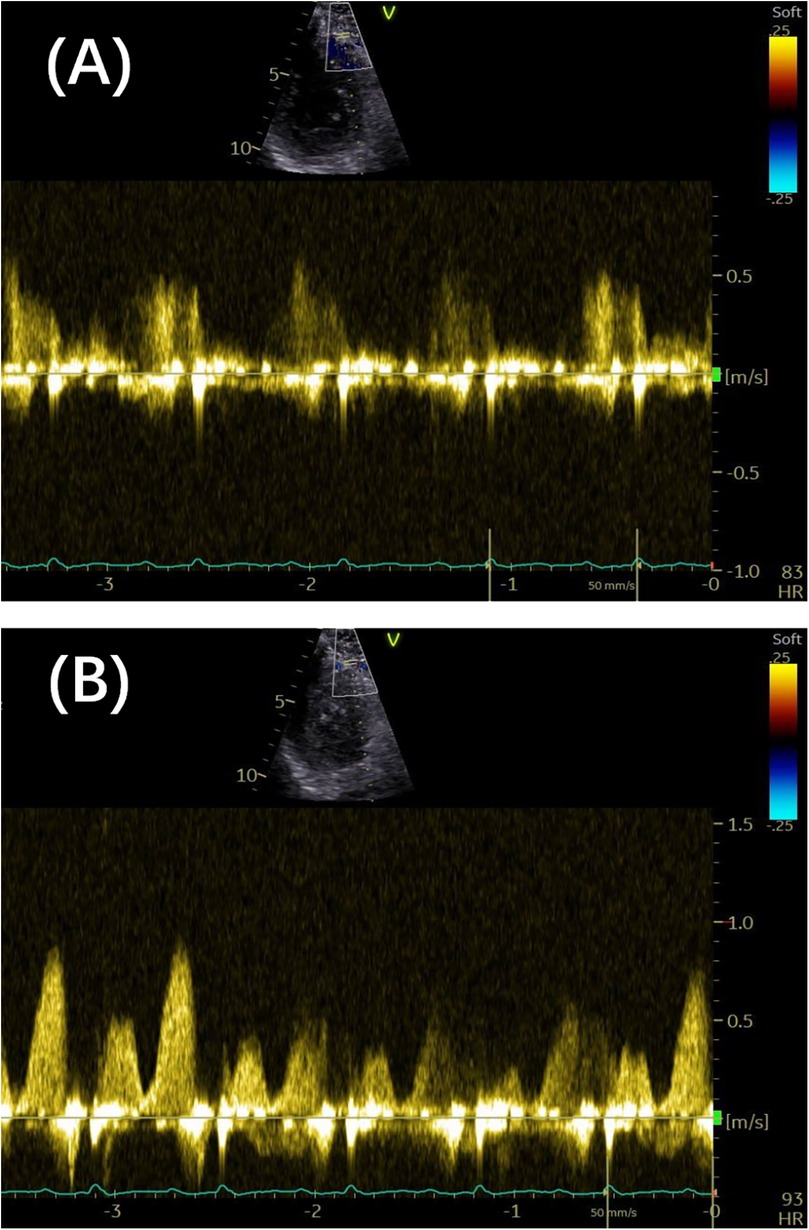

Previous studies have indicated that resting coronary velocity is higher when CFVR is lower. Several retrospective studies have highlighted the prognostic significance of coronary velocity, with prospective observations gradually complementing these findings. In a prospective study involving 747 patients, Zagatina et al. (5) evaluated the proximal left-sided artery segment and middle segments, with a resting coronary velocity exceeding 64–67 cm/s serving as the cutoff for predicting death, myocardial infarction, and MACEs. Additionally, the value of 65 cm/s stratified the patients into the three following groups: high risk of death or myocardial infarction at the incidence of 5.6% per year, as classified by increased velocity in the proximal left-sided artery segments; moderate risk at 2.3% per year, as stratified by increased velocity in the middle segments; and low risk at 0.3% per year, as characterized by any segment maximal velocity below 65 cm/s. Subgroup analyses of patients with known CAD, suspected CAD, arterial hypertension, valvular disease, and chest pain with unknown reason also supported the positive correlation between higher coronary velocity and increased incidence of death, myocardial infarction, and MACEs (5). A resting coronary flow velocity cutoff of 32 cm/s has also been associated with worse outcomes in patients with chronic coronary syndromes and preserved left ventricular ejection fraction (LVEF), adding incremental prognostic value to CFVR assessments (19). The emphasis on resting flow velocity is justified, as it should not merely serve as an auxiliary parameter for CFVR measurement. Increased baseline velocity may mechanistically contribute to reduced CFVR. Figure 3 illustrates high resting velocity coexisting with reduced CFVR.

Figure 3

(A) The distal LAD arterial flow velocity at rest was 0.58 m/s. (B) The distal LAD arterial flow velocity under vasodilator-induced hyperemia was 0.88 m/s. The coronary flow velocity reserve was 1.58. LAD, left anterior descending.